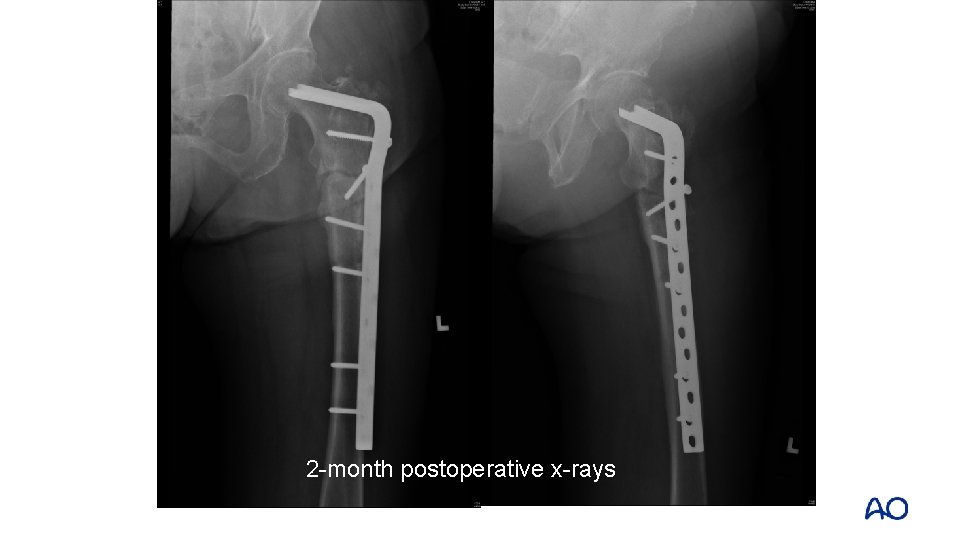

Angled blade plate refixation with allograft to femoral head in August 2011

2 -month postoperative x-rays